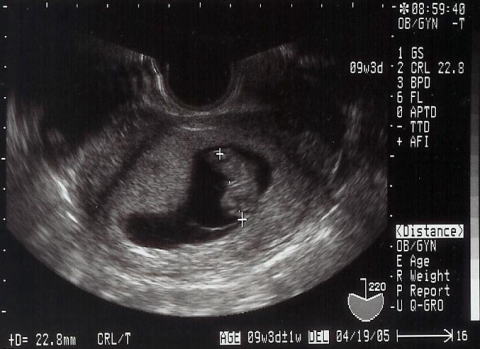

9週3日

ママの出血は続いています。今日は“正しく”安静にしていなかったということで、お医者様に怒られてしまいました。しかし、shigeruは元気です。22.8ミリ、10日で7.6ミリも大きくなっちゃった。少し形が見えてきたね。逆立ちしてバタバタ動いているの。